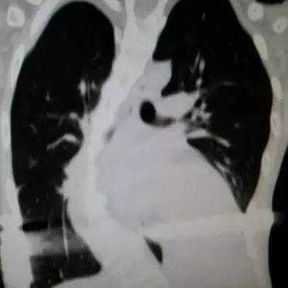

The patient is a 16-year-old male who has been diagnosed with pectus excavatum in childhood but experienced no discomfort in daily life. At the age of 15, he underwent Nuss procedure during which a bar was placed in his chest wall. However, the depression in his chest wall persisted after the surgery, and he even developed new severe deformities. As the deformities gradually worsened, the patient developed scoliosis, and his entire chest wall became completely distorted, eventually losing its basic shape. Later, the patient underwent another minimally invasive surgery for spontaneous pneumothorax, during which the surgeon ligated bilateral pulmonary bullae without treating the chest wall deformities. Ultimately, because of the severe deformities and breathing discomfort, the patient came to our hospital for treatment.

The patient was diagnosed with severe complex chest wall deformities accompanied by scoliosis. The heart was severely compressed and shifted to the left thoracic cavity.

We developed a personalized surgical plan for the patient. The operation first involved making incisions along the surgical scars on both sides of the chest wall to remove the bar inserted during the Nuss procedure. Then, a larger incision was made at the central scar on the anterior chest wall to fully expose the bone structure located at concave and convex areas of the chest wall. It was found that there were severe adhesions between the chest wall structure and the pericardium, with the heart being compressed into the left chest cavity.